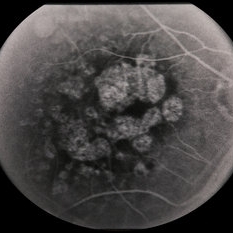

---thumb.jpg/image-square;max$300,300.ImageHandler) Age Related Macular Degeneration - Geographic Atrophy

Age Related Macular Degeneration - Geographic Atrophy

May 3 2013 by Suber S. Huang, MD, MBA, FASRS

Geographic Atrophy.

Imaging device: Retina Diseases Imaging Analysis Reading Center

Condition/keywords: advanced geographic atrophy, atrophic scar, atrophic spot, geographic atrophy, macula lesion, pigment epithelial atrophy